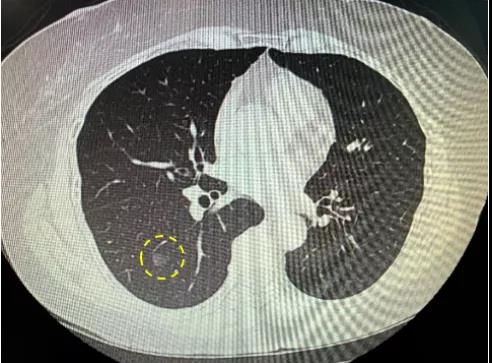

小時候覺得考一百分是最驕傲的事情,成年后才知道,原來拿到一份不亮紅燈的體檢報告才是...

前些天,朋友回奶奶家看老人,發現奶奶的桌上堆滿了大大小小的體檢報告單,奶奶說是村里...